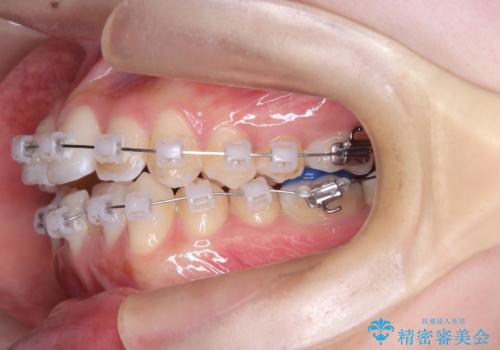

- クリア装置 ワイヤー

精密矯正検査を行った結果、歯を抜かずに行う、非抜歯のワイヤー矯正で治療を行う方針となりました。

治療計画をしっかり立て、歯の移動量や力のコントロールを最適化することで、約1年という短期間で矯正治療を終了することができました。